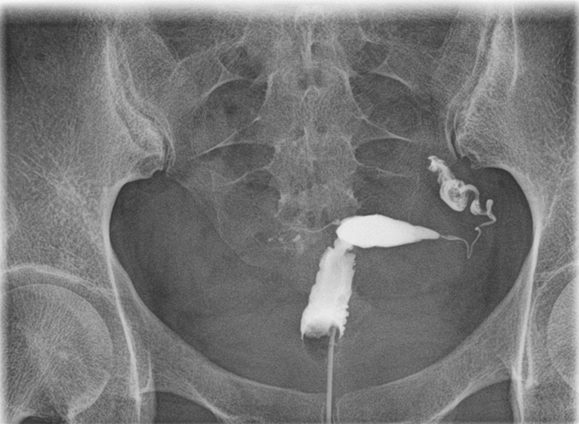

Ứ dịch vòi trứng (Hydrosalpinx)

Viêm dạng nốt đoạn eo vòi trứng (Salpingitis isthmica nodosa)